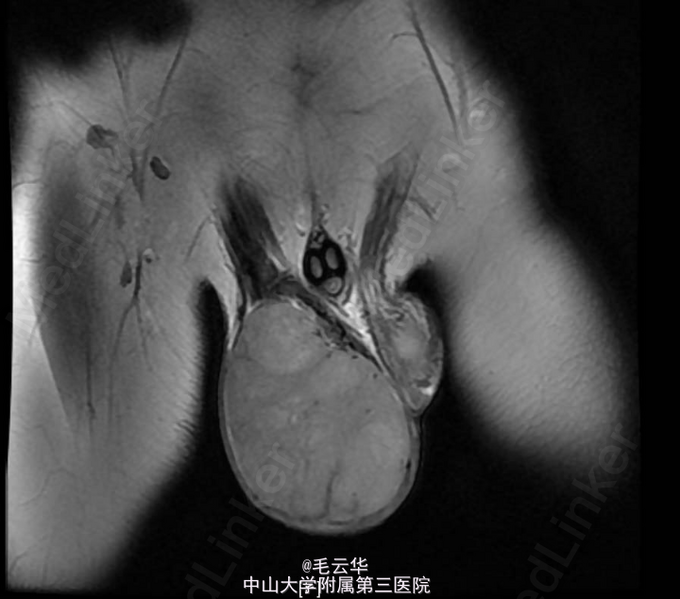

入院诊断:睾丸肿物性质待查 入院完善相关检查,尿常规:白细胞计数36.2个/ul↑;性激素六项:垂体泌乳素:1068.78 uIU/mL↑(48-375),雌二:164.56 pmon/L↑ (<146.1),睾酮14.77 nmol/L ↑ (0.5-2.6),促黄体生成素:1.87 uIU/mL ↓(3.1-34.6);血清人绒毛膜促性腺激素正常;CA199,CA125,CA153正常。阴囊超声检查结果示:右侧阴囊内实性肿块回声(120*71*68mm),边界清楚,内部回声不均匀,可见条索状高回声,考虑睾丸来源肿瘤性病变可能。左侧睾丸超声检查未见明显异常。 左侧附睾超声检查未见明显异常。肝、胆、胰、脾、肾、输尿管、膀胱、腹腔淋巴结超声检查均未见明显异常。MR示:右侧阴囊内占位,考虑睾丸来源恶性肿瘤,精原细胞瘤可能大。行右侧睾丸切除术,标本送病理。术后病理显示右侧睾丸肿物精原细胞瘤;“切缘”未见肿瘤。术后患者拒绝对同侧髂淋巴结和腹膜后淋巴结进行预防性放疗,嘱定期返院随访,办理出院。出院诊断右侧睾丸精原细胞瘤。